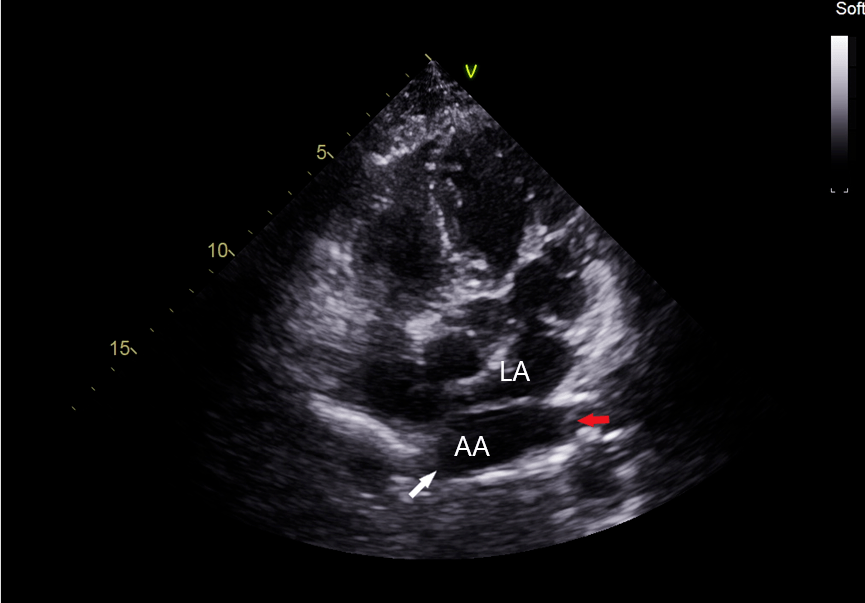

口,短箭头所示隔膜la : 真房, lv :左室,aa :副房图 1 心尖五腔心切面

图片尺寸865x603